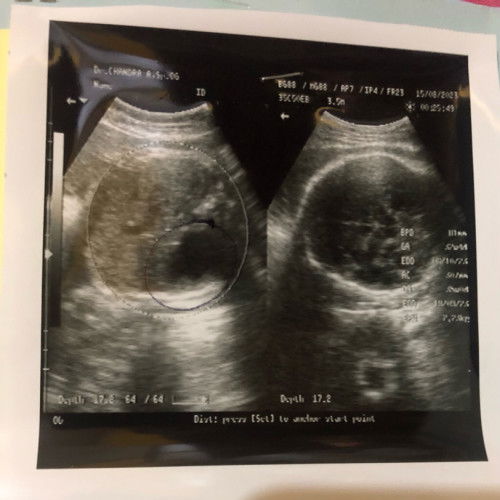

Dokter yg USG saya mendiagnosa janin saya Atresia Duodenum

Halo bund, mau tanya kehamilan saya sekarang 35 week dokter yg USG saya mendiagnosa janin saya terkena Atresia duodenum dan langsung di rujuk untuk ke Klinik Fetomaternal Gulardi Centre. Apakah bunda punya kasus yg sama seperti saya yg di haruskan untuk ke klinik tersebut? Jika iya, apakah di klinik tersebut bisa pake BPJS? Saya ragu dengan USG dari dokter tersebut mengingat USG sebelumnya / dokter yg berbeda bilang janin saya normal ga ada kelainan apapun. #ingintahu #firstmom #pleasehelp